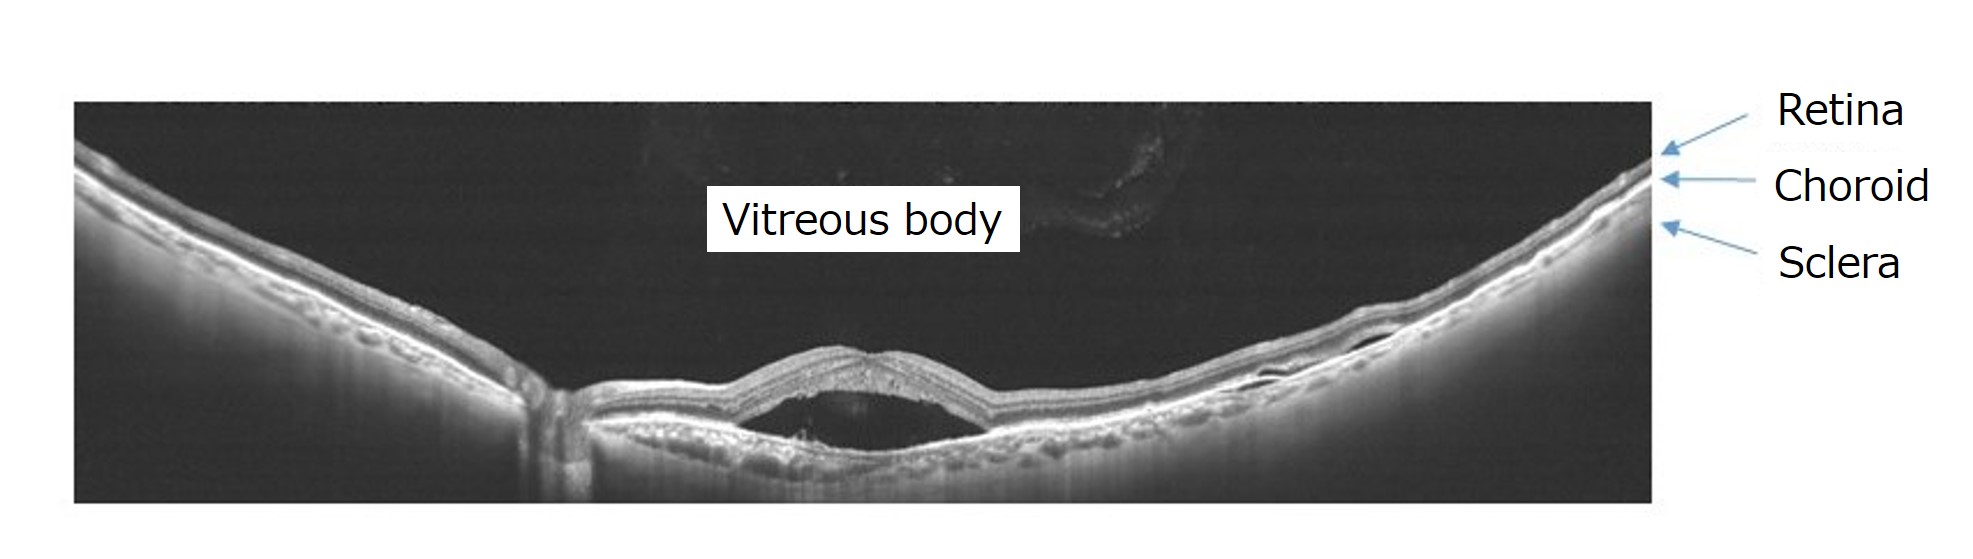

Технологія частотно-модульованого джерела Swept Source (SS), яка забезпечує високошвидкісне сканування, використовується для отримання ширококутного глибокого зображення з шириною сканування 23 мм і глибиною приблизно 5,3 мм. Частотно-модульоване джерело світла швидко випромінювати довгі хвилі. Світло може проникати глибоко в очне дно, але відбите світло має бути швидко оброблено в цифрові сигнали, інакше зображення неможливо отримати вчасно. Для отримання зображень за допомогою високошвидкісних обчислень використовується високопродуктивна плата аналого-цифрового перетворення. У минулому томографічні зображення очного дна з великою осьовою довжиною (довжина очного яблука в передньо-задньому напрямку), наприклад, у випадках високої короткозорості, не могли бути правильно відтворені. Тепер технологія Canon дозволяє отримати зображення з високою роздільною здатністю величезної області від склоподібного тіла до сітківки, судинної оболонки та межі склер за один сеанс, дозволяє виявити відшарування сітківки та крововиливи.

Зображення високої чіткості широкого діапазону за один знімок (ОКТ і томографічні зображення) (рис.4)